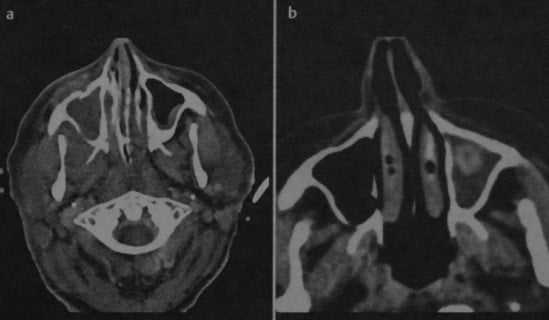

(Справа) При аксиальной КТ без КУ определяется односторонний аллергический грибковый синусит. Пораженные пазухи вздуты и содержат плотный «выветренный» материал в центре, окруженный гиподенсным ободком по периферии. Поражение пазух при АГС может быть одно- или двухсторонним.

(Справа) На аксиальной КТ без КУ определяется односторонний АГС. Пораженные пазухи вздуты, сдержат уплотненный материал в центре, окруженный гиподенсным периферическим «ободком». Поражение пазух при АГС может быть одно- или двухсторонним.